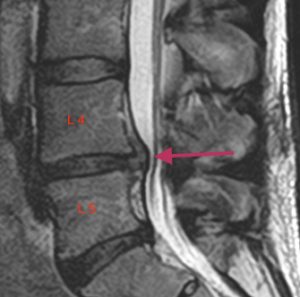

Lannerangan magneettikuva 1

Lannerangan sivuprofiili (sagittaalikuva).

Magneettikuvausta käytetään runsaasti lannerangan vaivojen selvittelyssä. Kuvissa nähdään selkäytimen rakenne sekä hermoja mahdollisesti painavat muutokset kuten välilevyn pullistumat, selkäytimen ahtaumat tai nikamasiirtymät.